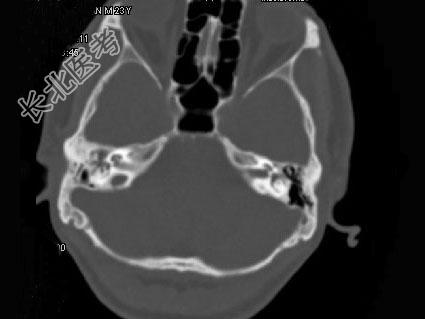

- 单项选择题男,23岁,右耳流脓十余年,右外耳道流脓,鼓膜穿孔,CT检查如图,最可能诊断为 ( )